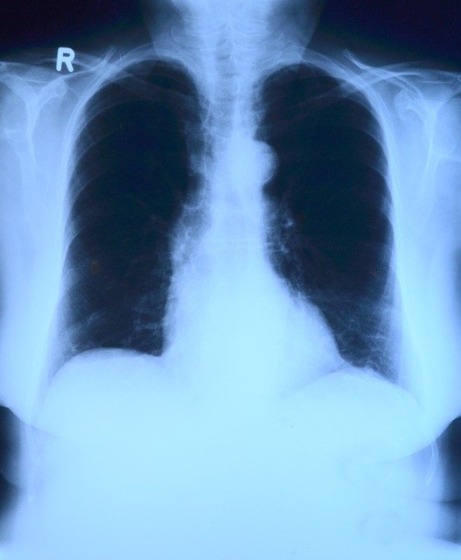

人体のレントゲン写真

toubibe

交通事故による怪我を治療できる治療院の1つは整形外科です。整形外科は、主に医師が治療を行い、レントゲやMRIなどの機器を使って骨の異常を検査します。

そして、その結果に応じて必要な場合は手術を行います。痛みがなかなか引かない場合は、湿布や痛み止めの処方も施してくれる治療院です。

特に、自覚症状が無い場合は、どこが怪我しているかも気づけないケースもあります。そのため、交通事故にあった場合は、まずは整形外科を受診して細かく検査しましょう。

整形外科では、レントゲンやMRIなどの機器を使って精密な検査を行うことができます。そのため、交通事故に遭った際に、自覚症状がない場合や痛くないときは、まず整形外科で細かな検査をしましょう。

そして、整形外科を受診した際は、医師に診断書を作成してもらいましょう。診断書はケガと交通事故との因果関係を明らかにするために重要な書類です。